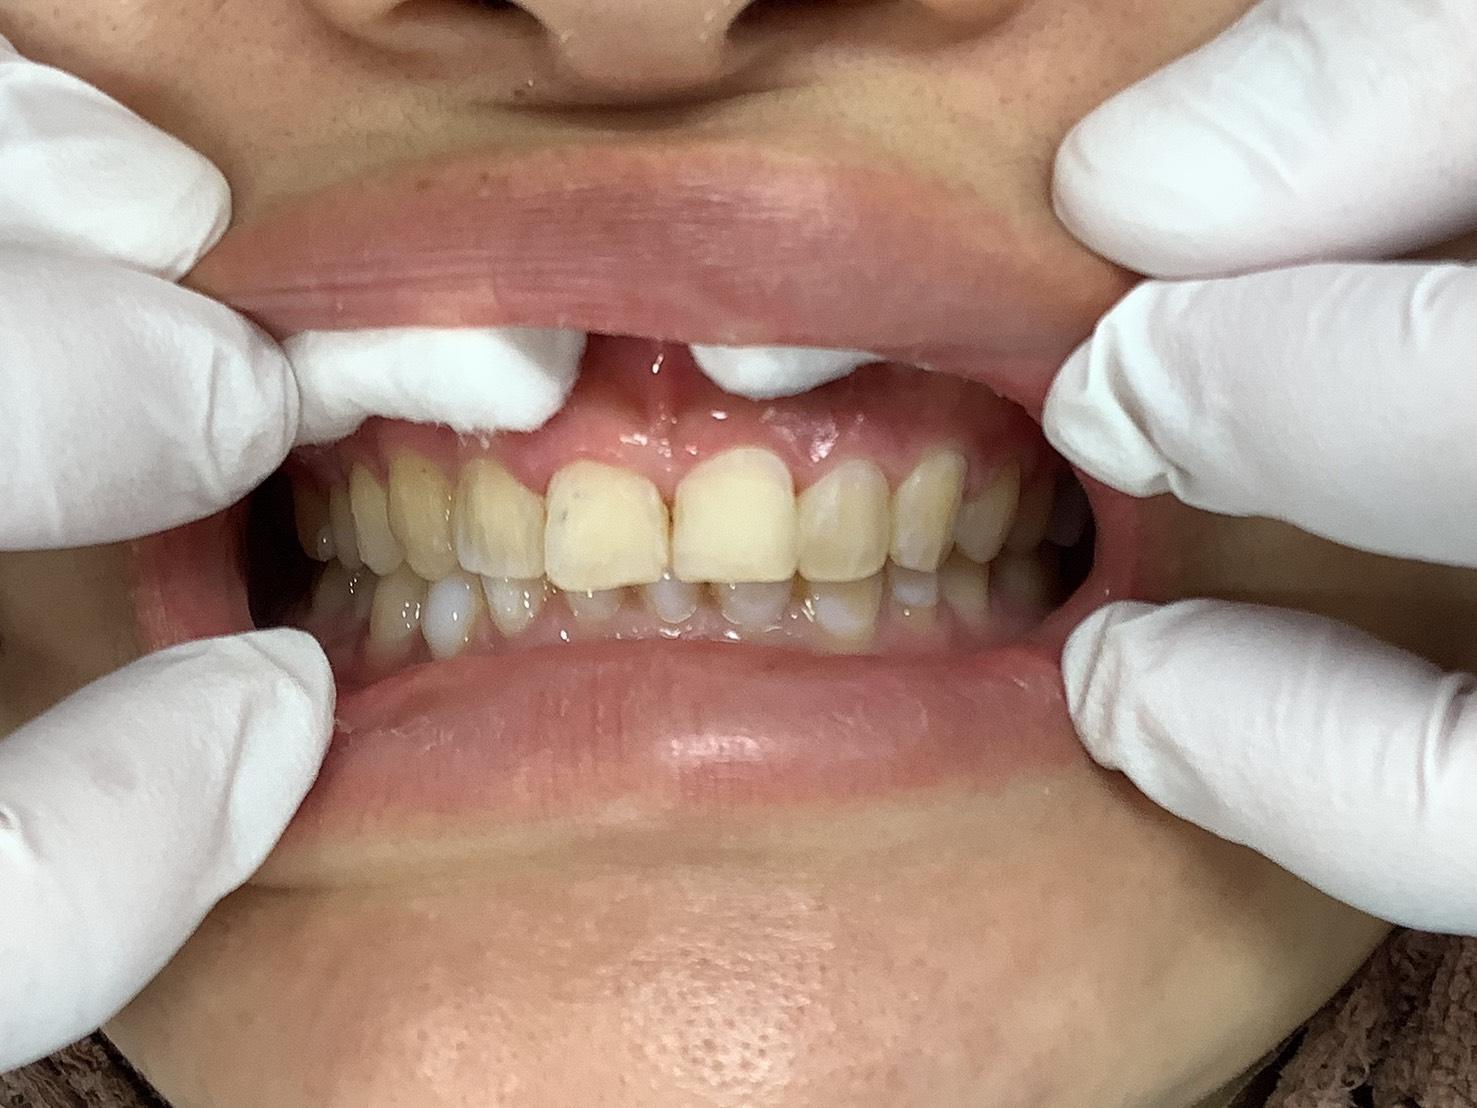

CASE 10

BEFORE

▶

AFTER

20代。 「前歯がデコボコしているのが気になる」「笑った時に歯並びが悪く見える」というお悩みでご来院。 仕事やプライベートで目立つワイヤー矯正は避けたいとのことで、透明なマウスピース矯正をご希望されました。